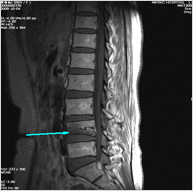

척추압박골절 - 사진

척추압박골절

정의

뼈속의 칼슘이 빠지면서 척추뼈가 약해져 가벼운 충격(삐끗하거나 넘어질 경우)으로도 척추뼈가 눌리는 골절이 발생 할 수 있다.

증상

심한 요통과 압통으로 눕거나 일어날 때 심하게 통증을 호소하며 골절된 부위를 가볍게 두드려도 통증을 호소한다.

원인

골다공증으로 약해진 척추뼈가 충격에 의해 손상.